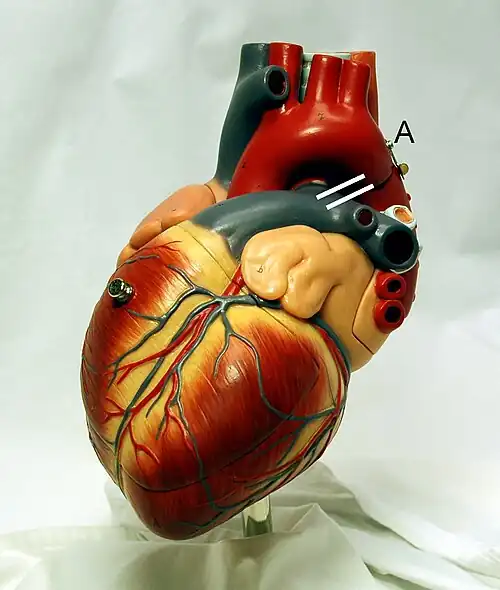

The Heart

The heart is a hollow, muscular organ about the size of a fist. It is responsible for pumping blood through the blood vessels by repeated, rhythmic contractions. The heart is composed of cardiac muscle, an involuntary muscle tissue that is found only within this organ. The term "cardiac" (as in cardiology) means "related to the heart” and comes from the Greek word kardia, for "heart." It has a four-chambered, double pump and is located in the thoracic cavity between the lungs. The cardiac muscle is self-exciting, meaning it has its own conduction system. This is in contrast with skeletal muscle, which requires either conscious or reflex nervous stimuli. The heart's rhythmic contractions occur spontaneously, although the frequency or heart rate can be changed by nervous or hormonal influence such as exercise or the perception of danger.

Heart Chambers

The heart has four chambers, two atria and two ventricles. The atria are smaller with thin walls, while the ventricles are larger and much stronger.

The ventricle is a heart chamber which collects blood from an atrium and pumps it out of the heart. There are two ventricles: the right ventricle pumps blood into the pulmonary artery which takes the blood through the pulmonary circuit, and the left ventricle pumps blood into the aorta for systemic circulation to the rest of the body. Ventricles have thicker walls than the atria, and thus can create the higher blood pressure. Comparing the left and right ventricle, the left ventricle has thicker walls because it needs to pump blood to the whole body. This leads to the common misconception that the heart lies on the left side of the body.

Coronary Arteries

Heart showing the Coronary Arteries The coronary circulation consists of the blood vessels that supply blood to, and remove blood from, the heart muscle itself. Although blood fills the chambers of the heart, the muscle tissue of the heart, or myocardium, is so thick that it requires coronary blood vessels to deliver blood deep into the myocardium. The vessels that supply blood high in oxygen to the myocardium are known as coronary arteries. The vessels that remove the deoxygenated blood from the heart muscle are known as cardiac veins. The coronary arteries that run on the surface of the heart are called epicardial coronary arteries. These arteries, when healthy, are capable of auto regulation to maintain coronary blood flow at levels appropriate to the needs of the heart muscle. These relatively narrow vessels are commonly affected by atherosclerosis and can become blocked, causing angina or a heart attack. The coronary arteries are classified as "end circulation", since they represent the only source of blood supply to the myocardium: there is very little redundant blood supply, which is why blockage of these vessels can be so critical. In general there are two main coronary arteries, the left and right. • Right coronary artery • Left coronary artery Both of these arteries originate from the beginning (root) of the aorta, immediately above the aortic valve. As discussed below, the left coronary artery originates from the left aortic sinus, while the right coronary artery originates from the right aortic sinus. Four percent of people have a third, the posterior coronary artery. In rare cases, a patient will have one coronary artery that runs around the root of the aorta.